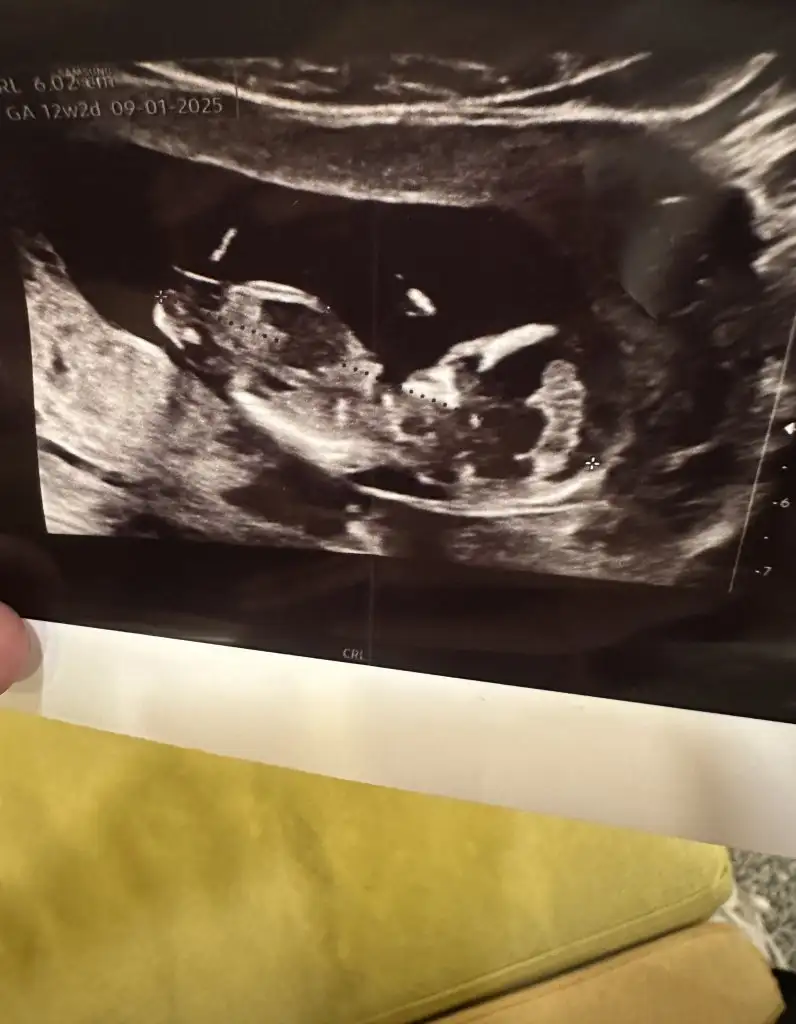

Evett güncelleme yapıyorum son ultrason fotoğrafımız 🤍 düşüncesi olan var mı 🥰

• IMG_5851.webp

IMG_5851.webp

42,2 KB · Görüntüleme: 103